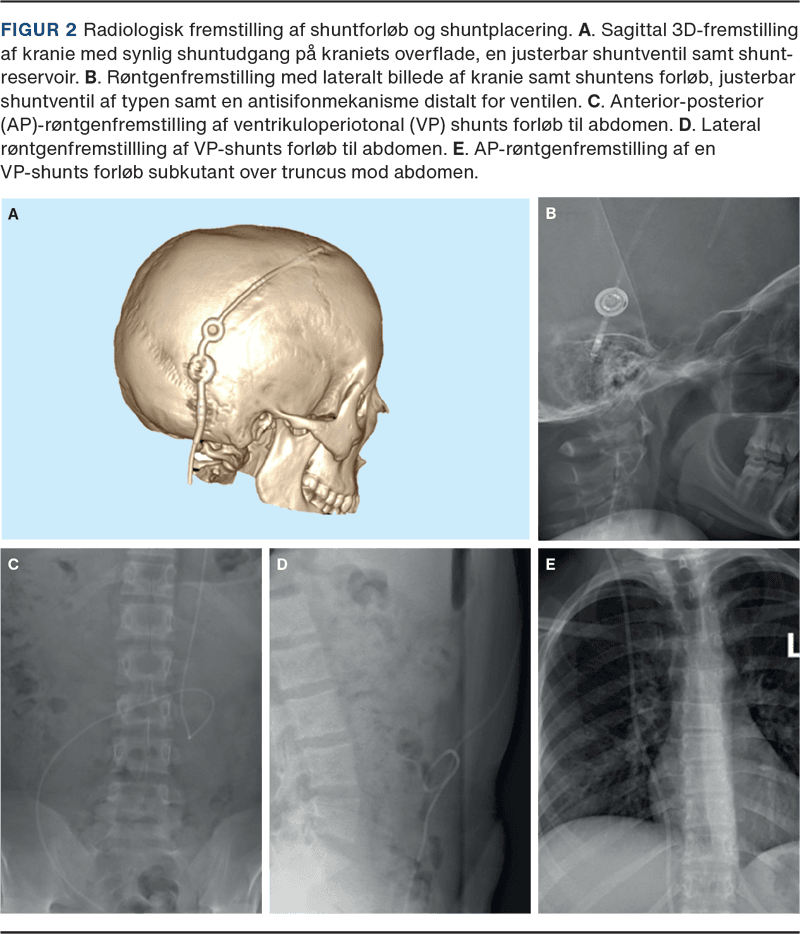

Radiologisk billeddiagnostik har en stor plads i shuntdysfunktionsudredning (Figur 2). Konventionel røntgenundersøgelse anvendes til billedfremstilling af shuntserier, hvor projektionerne anterior-posteriort plan og lateralplan kan fremstille shuntens forløb kranielt, torakalt og abdominalt. CT eller MR-skanning af cerebrum anvendes til vurdering af cerebral ventrikel-størrelse, subdurale ansamlinger (hygromer, hæmatomer) og udelukkelse af differentialdiagnoser. Uændrede intrakranielle forhold udelukker dog ikke shuntdysfunktion.

En shunt består oftest af fire komponenter: proksimalt kateter, reservoir, ventil og distalt kateter. Forudgået af et borehul i kraniet indføres det proksimale kateter i en af de cerebrale lateralventrikler, mens det distale kateter indføres på lokationen for CSV-absorption. Shuntslangen løber altid subkutant fra kranie til indløbsstedet. Ventilens primære funktion er ensretning af flow væk fra de cerebrale ventrikler, og reservoirets beliggenhed oven på kraniet muliggør palpation og punktur [4, 17].